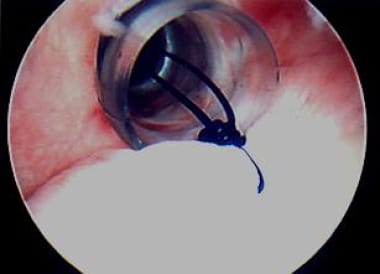

Next, with monofilament suture employed in an all-arthroscopic knot-tying technique (sliding knot first, backed up by an alternating post, alternating half-hitch technique), a knot is tied, plicating the capsular pinch to the labrum (see the image below).

Next, with monofilament suture and all-arthroscopic knot-tying technique, knot is tied, thus plicating capsular "pinch" to labrum. Photo courtesy of Daniel C Wnorowski, MD.